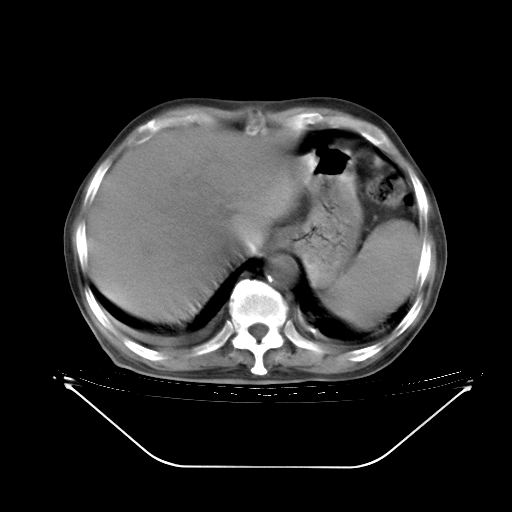

胸腹部CT,诊断意见:左上肺叶钙化灶、左侧胸膜局限性增厚并钙化、胆囊炎。描述部分肺组织呈磨玻璃样改变。

今天复查肺部CT,发现双肺广泛磨玻璃样改变。所以我把3月19日和5月9日相隔50天的肺部CT上传。请大家会诊。

5月9日肺部CT(在4月27日齐鲁医院肺部CT描述部分肺组织磨玻璃样改变,12天后肺组织广泛磨玻璃样改变)

2009年5月9日肺部CT

大致读了系列胸部CT:纵隔窗无明显异常,肺窗:从4、27至今:主要是双肺中下野外带可见毛玻璃样改变,目前处于急性肺泡炎阶段,至于原因考虑1、结替组织或胶原血管性疾病所致?2、恶性疾病如恶组在肺部所致的表现或细支气管肺泡癌?3、药物或其它原因如肺蛋白沉着症所致肺泡炎目前不太可能?总之,明天就去请我院的呼吸科、感染科、血液科和临免专家会诊哈。